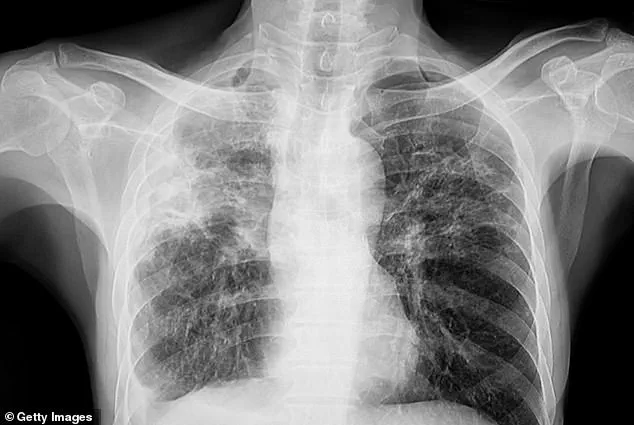

Tuberculosis, which primarily affects the lungs, is caused by the bacterium *Mycobacterium tuberculosis* and spreads through the air when an infected person coughs, sneezes, or speaks.

The symptoms of TB can be insidious in their early stages, often manifesting as a persistent, unexplained cough that may be accompanied by coughing up blood or chest pain.

As the disease progresses, patients may experience unexplained weight loss, loss of appetite, fever, and night sweats—symptoms that can be easily mistaken for other illnesses.

In later stages, the infection can lead to severe breathing difficulties, extensive lung damage, and even the spread of the disease to other organs such as the liver or spine, causing localized pain.

Without timely treatment, TB can be fatal, as patients may succumb to respiratory failure or organ damage that prevents the body from adequately oxygenating the blood.